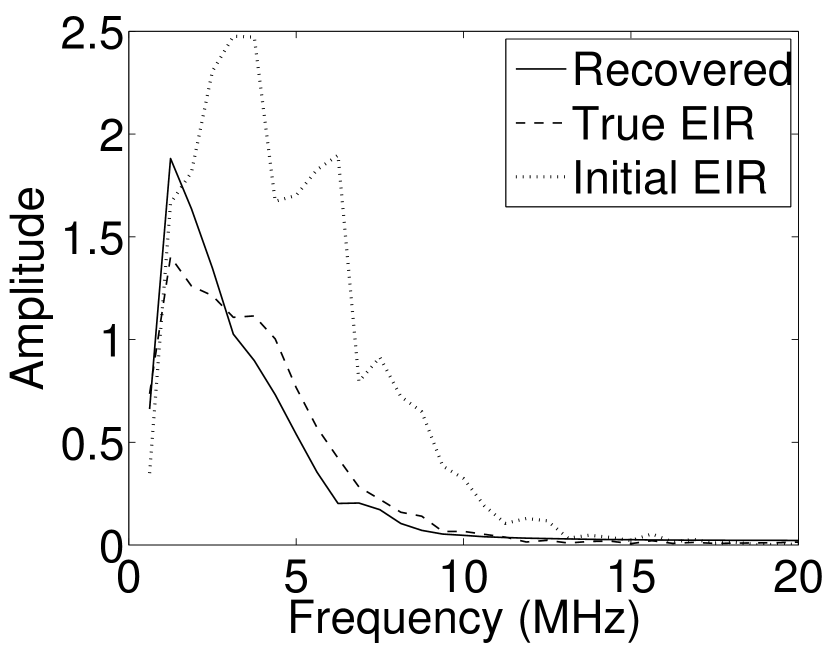

Images reconstructed by use of the VP algorithm with different values of the regularization parameter values are shown in Figure 8. The recovered EIRs and their corresponding Fourier spectra are shown in Figures 9 and 10, respectively. The RMSE values are computed and displayed together with the corresponding images. As expected, the images reconstructed with smaller values of contain higher noise levels, while images using larger possess a reduced noise level. However, larger values of also caused artifacts in the reconstructed images. The same observation can be made for the effect of the regularization parameter on the recovered EIR. One also observes that the reconstructed images and EIRs depend continuously on the regularization parameters and , i.e. small changes in the regularization parameters cause minor changes in the reconstructed images and EIRs.

VI Experimental validation